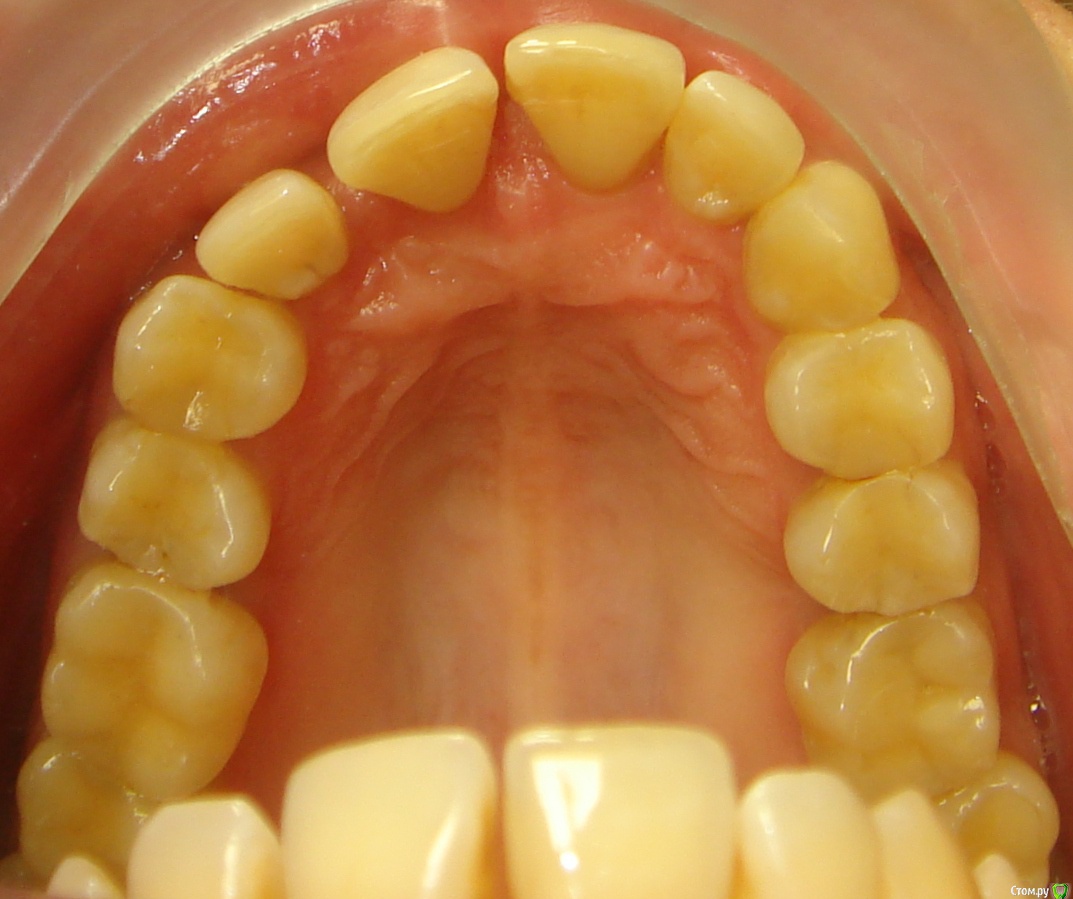

Opdihatop Опубликовано 9 мая, 2016 Поделиться Опубликовано 9 мая, 2016 (изменено) Здравствуйте, коллеги! Хотел бы представить вашему вниманию вот такой вот случай и спросить совета. В принципе, по окклюзии ничего особенного по лечению нет, но вот проблемы с пародонтом (на КТ по кости все заметно хуже, чем на орто), делают невозможным все, продуманные мной варианты. Может у кого-то было что-то подобное? Может поделитесь советом, а то помочь человеку надо, а я в тупике. Буду заранее очень благодарен за помощь! Изменено 9 мая, 2016 пользователем Opdihatop Ссылка на комментарий

Opdihatop Опубликовано 11 мая, 2016 Автор Поделиться Опубликовано 11 мая, 2016 Я думал сделать тут SARPE и поставить небный расширитель, который крепится не к зубам, а к кости под слизистой (не помню, как называется), на н/ч планировал удалять один резец и работать на самолигах, но вот боюсь еще большей потери кости. А Вы как думаете? Ссылка на комментарий

Yana guapa Опубликовано 12 мая, 2016 Поделиться Опубликовано 12 мая, 2016 показаний к сарпе здесь нет. дать разобщение и перебросить боковые зубы кросс тягой. внизу бы не удаляла. на самолигах итак места достаточно будет. ну максимум стриппинг. были такие пациенты, что думала зубы с лигатурами вылетят ... но ничего! к концу лечения укрепились даже! все на месте! просто у таких пациентов еще нежнее надо 1 Ссылка на комментарий

Yana guapa Опубликовано 13 мая, 2016 Поделиться Опубликовано 13 мая, 2016 1) Здесь главное, что волнует пациентку, это создание места под 13 зуб. Да, она согласна корректировать все остальные проблемы, но не пойдет на лечение, если "ее" цель не будет достигнута. И да, я понимаю, что идеала тут достичь у меня не получится. под 1.3. зуб место создадите без проблем. Но если Ваша пациентка мечтает о голливуде (может еще и о новом пародонте?) , то лучше ее вообще не брать. Пусть радуется хоть тому, что вообще можно слепить. 2) Так уж сложилось, что кросс-эластиками я не так уж много работал, как то пациенты не подворачивались. По-этому позвольте в связи с этим вопрос: а не навредит ли нам тут вестибулярный наклон верхних моляров, который несомненно возникнет за счет тяги (они наклонены орально незначительно)? Да, я понимаю, что и нижние наклонятся орально, но все же. у вас не будет чистого вестибулярного наклона верхних моляров, потому что помимо кросс-эластиков у вас будут хорошие расширяющие дуги, придающие нужную форму зубному ряду. плюс кросс-тяги. и конечно хорошее разобщение. 3) Почему Вы против, пусть даже не сарпе, так хоть послабления небного шва в этом случае? С трудом верится, что в этом возрасте, пусть даже на самолигах, получится получить стабильное расширение. если Вам там хочется поставить RPE поставьте) но вы всегда можете это успеть сделать, в случае неудачи кросс тяг. заранее обговаривается. (тем более это дополнительные финансовые траты) 4) Я встречал в литературе успешное применение, при подобном пародонте, дистализации на в/ч при непрямом анкораже на м/и. Подобное лечение (с нормальной костью) неоднократно производил и успешно. Как Вы считаете, рискнуть или успех маловероятен? а что Вы дистализировать здесь хотите? Ссылка на комментарий

Opdihatop Опубликовано 13 мая, 2016 Автор Поделиться Опубликовано 13 мая, 2016 Благодарю за ответы! а что Вы дистализировать здесь хотите? под 1.3. зуб место создадите без проблем. Но если Ваша пациентка мечтает о голливуде (может еще и о новом пародонте?) , то лучше ее вообще не брать. Пусть радуется хоть тому, что вообще можно слепить. Видимо опыта у меня мало... А как место под 13, да еще и без проблем, создать? :-) Существующие тремы уйдут за счет ретрузии фронта, а одного расширения, пусть даже с РПЕ для 13 не хватит, вот для этого и думал дистализировать оба боковых сегмента в/ч хотя бы на 2 мм. Еще раз спасибо! :-) Ссылка на комментарий